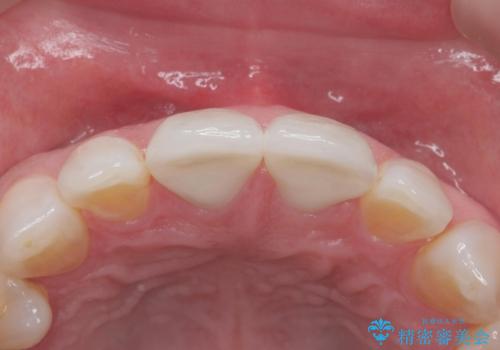

取れていない方のべニアも周囲の歯と色調が合っていなかったため、一緒にやり替えました。

脱離リスクを抑えつつ、審美性も確保できたことで大変喜んでいただけました。

- 右上1左上1 : 仮歯/11,000円×2、ジルコニアクラウン(スペシャル)/154,000円×2 合計330,000円(税込)費用は治療当時の料金となります